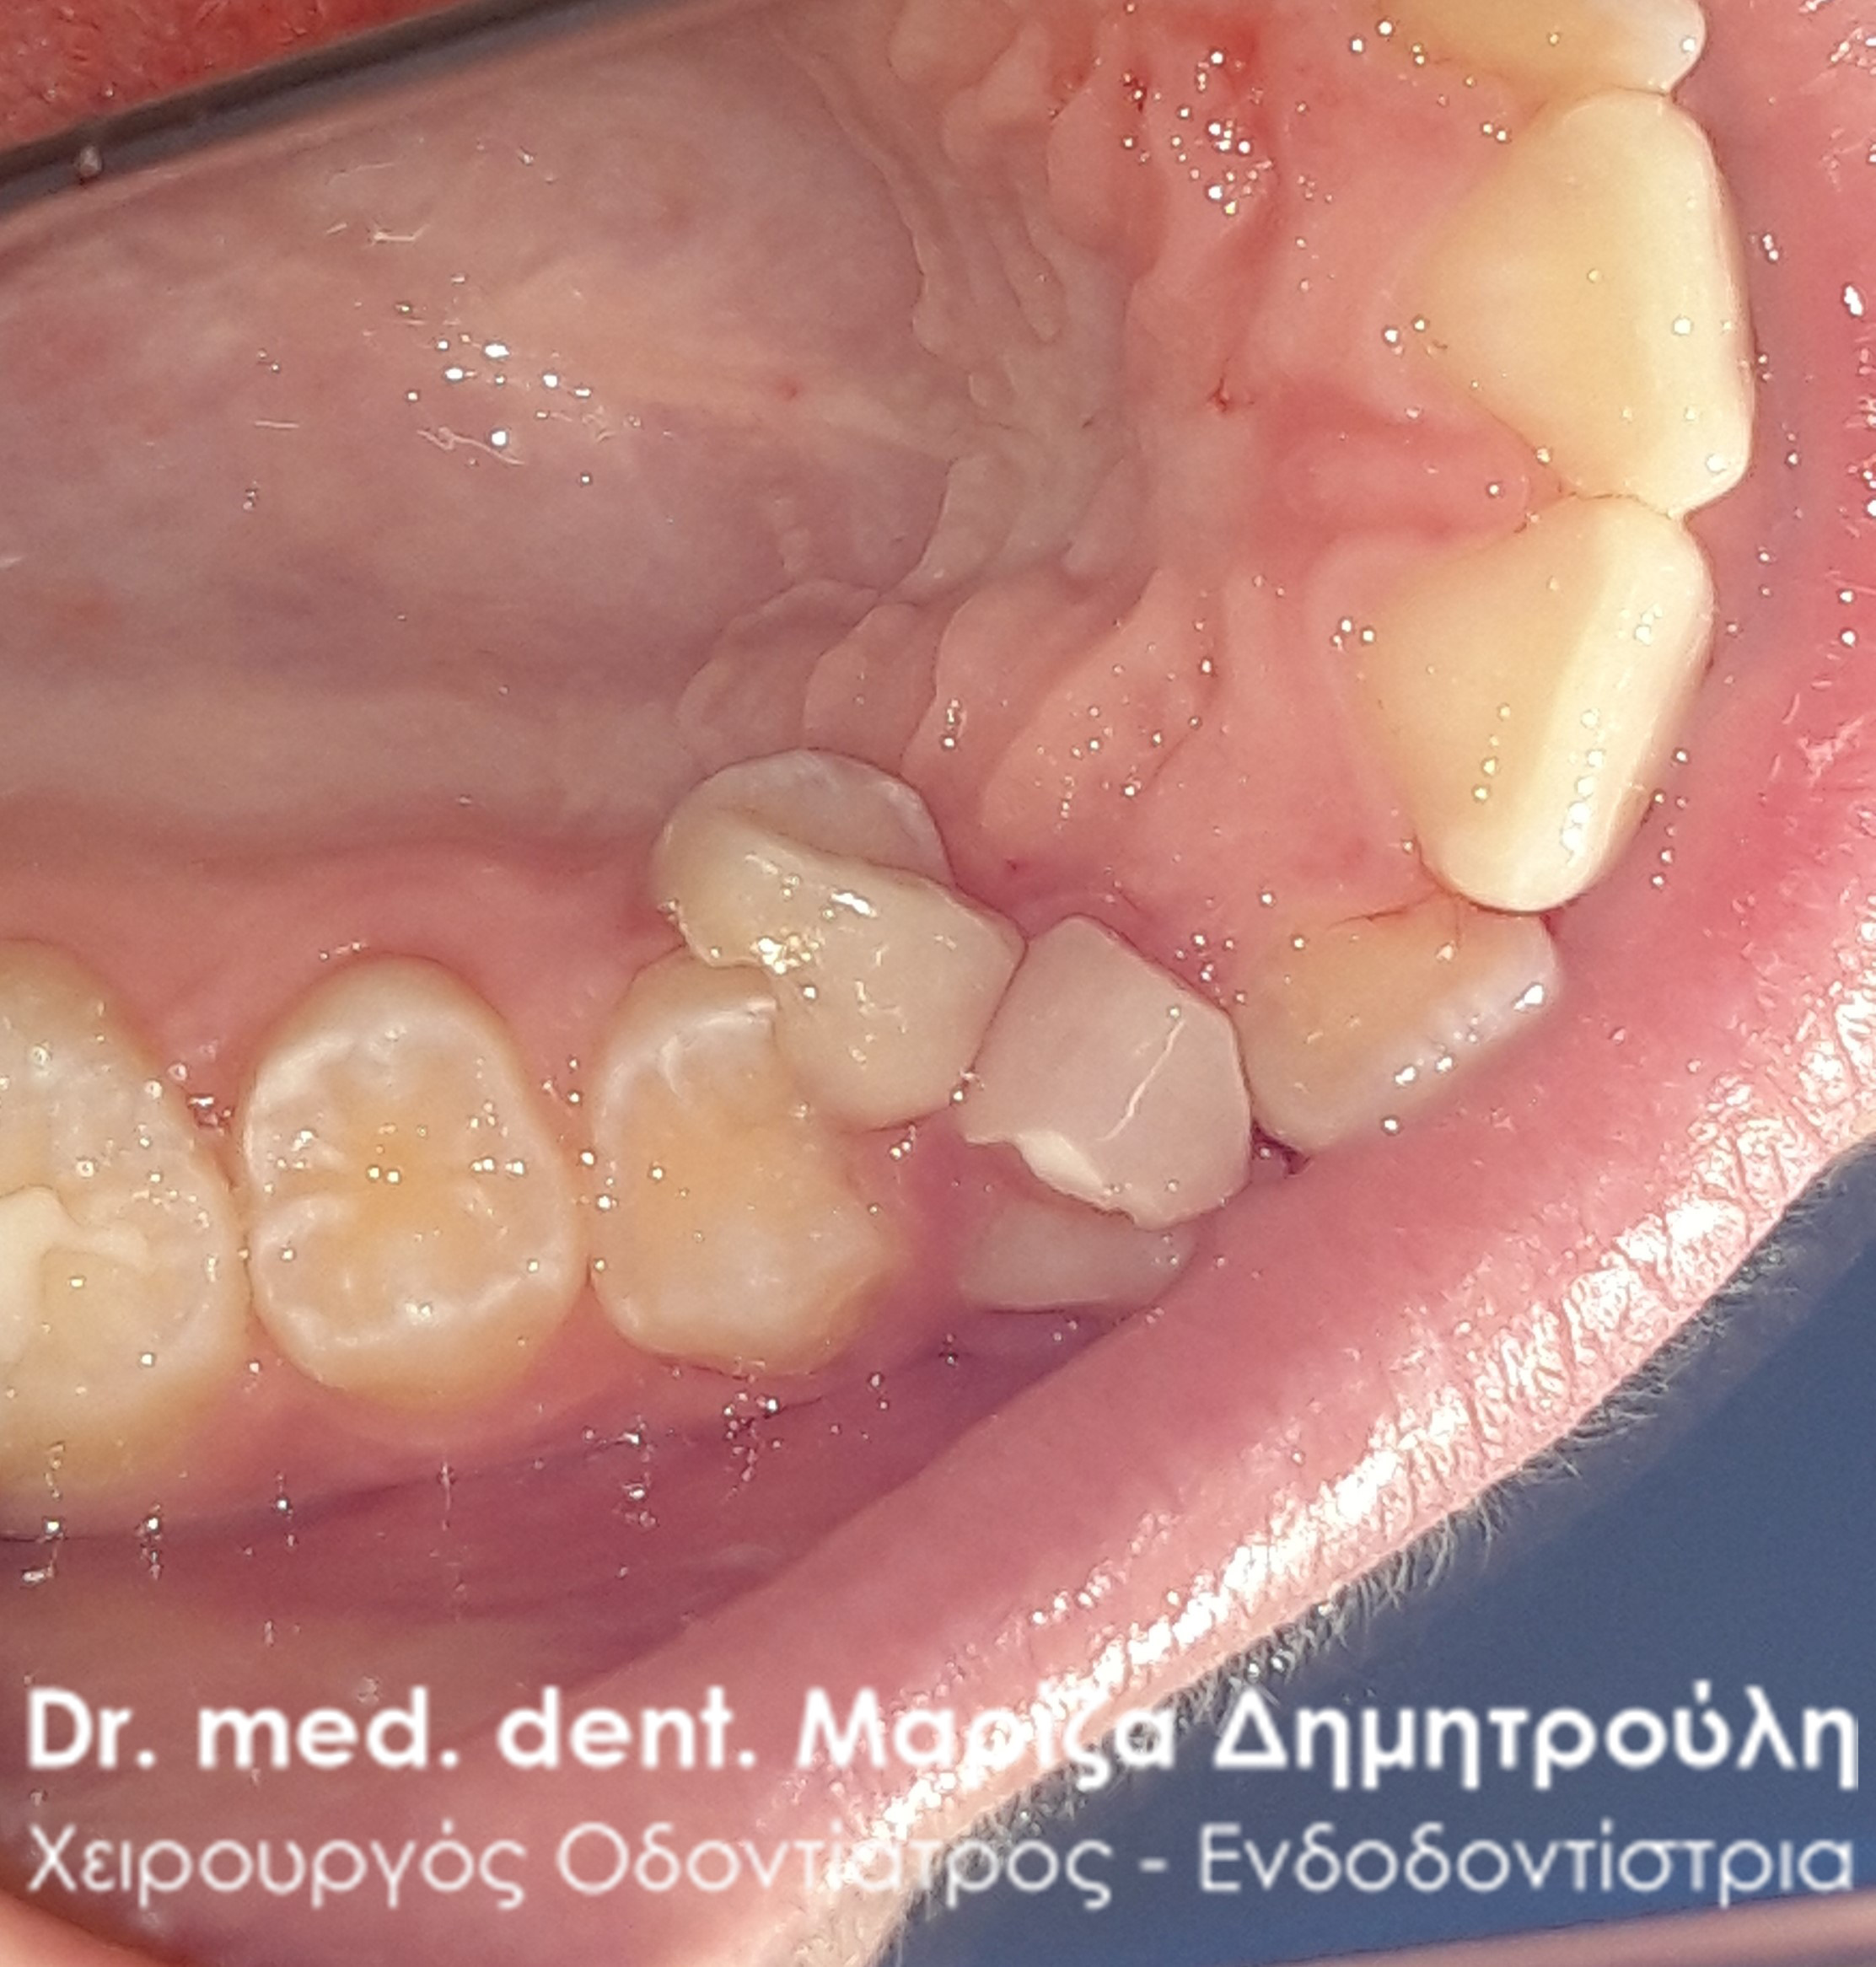

Η μαμά του μικρού νεαρού είχε τρομάξει καθώς τα δοντάκια του παιδιού της τον τελευταίο καιρό παρουσιάζουν την παρακάτω εικόνα που δείχνουν οι φωτογραφίες. Το πρόβλημα βέβαια ήταν πολύ απλό, καθώς για τη λύση του προβλήματος απαιτούταν μόνο η εξαγωγή των παιδικών δοντιών. Στην πραγματικότητα κάτω από τα παιδικά δοντάκια είχαν ήδη ανατείλει τα μόνιμα δόντια, τα οποία πίεζαν από κάτω τα αντίστοιχα παιδικά δοντάκια. Για αυτό το λόγο φαίνεται οι νεογιλοί τομείς να είναι στον αέρα. Το αισθητικό πρόβλημα αντιμετωπίστηκε άμεσα με την εξαγωγή των παιδικών δοντιών.